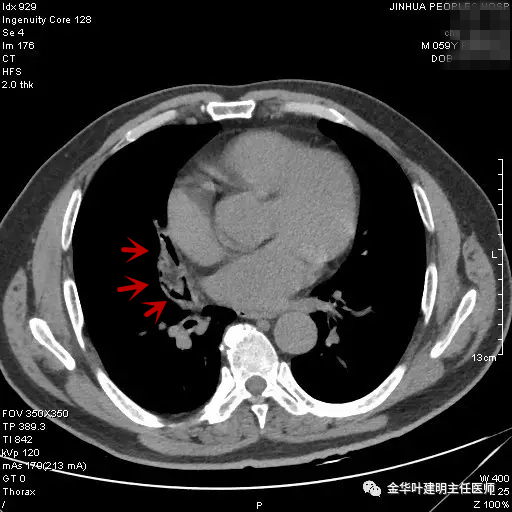

患者陈某,金华人,前一年的11月份因外伤到医院检查胸部CT时,发现右肺中叶异常,以下是CT图片与报告:

胸部CT:右肺中叶及下叶慢性炎症,部分支气管管腔略变窄,建议复查。

图二示:第1次胸部CT时的纵隔窗